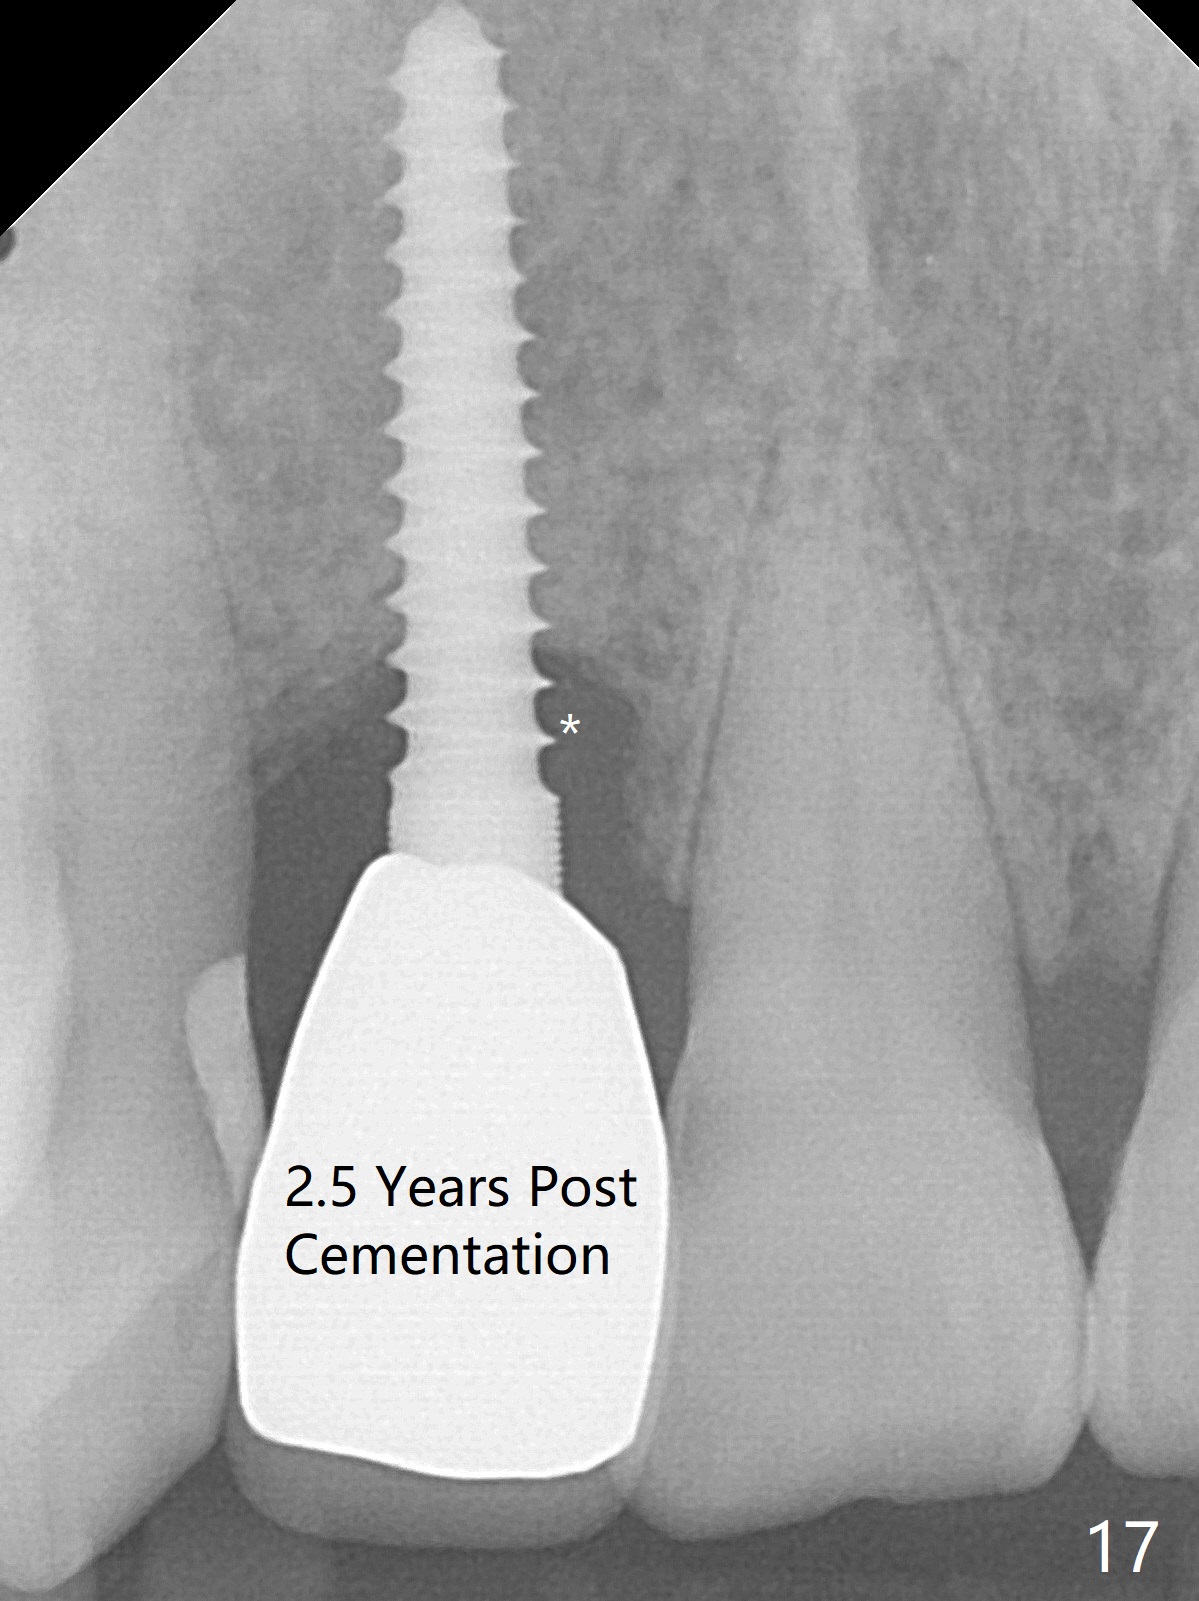

Sixteen days postop, the patient is doing fine, although the labial fistula has not disappeared (Fig.8 <). The detached distolabial papilla is healing (Fig.9 *) with mild bone graft exposure (^). The lacerated distopalatal papilla is also healing (Fig.10 *). These complications are related to flap surgery. The apical portion of the socket appears to have reduced 4 months postop (Fig.14). When the definitive restoration is delivered 5 months postop, there is gingival recession, including the distal of #8 (Fig.11 arrows, which is expected to improve over time) due to flap surgery. The labial plate collapse is minimal (Fig.12 *), while the palatal laceration (Fig.10) has healed (Fig.13). When the patient returns 1.5 years post cementation, there is increased bone density next to the coronal portion of the implant, equivalent to the bone graft (Fig.15 *). The fistula is absent (Fig.16). The crestal bone loss remains 2.5 years post cementation (Fig.17 *), although there is no sign of periimplantitis (magnification). Oral hygiene is poor. There is no change in the soft (gingival recession; data not shown) or hard tissues 3 years 8 months post cementation (Fig.18).